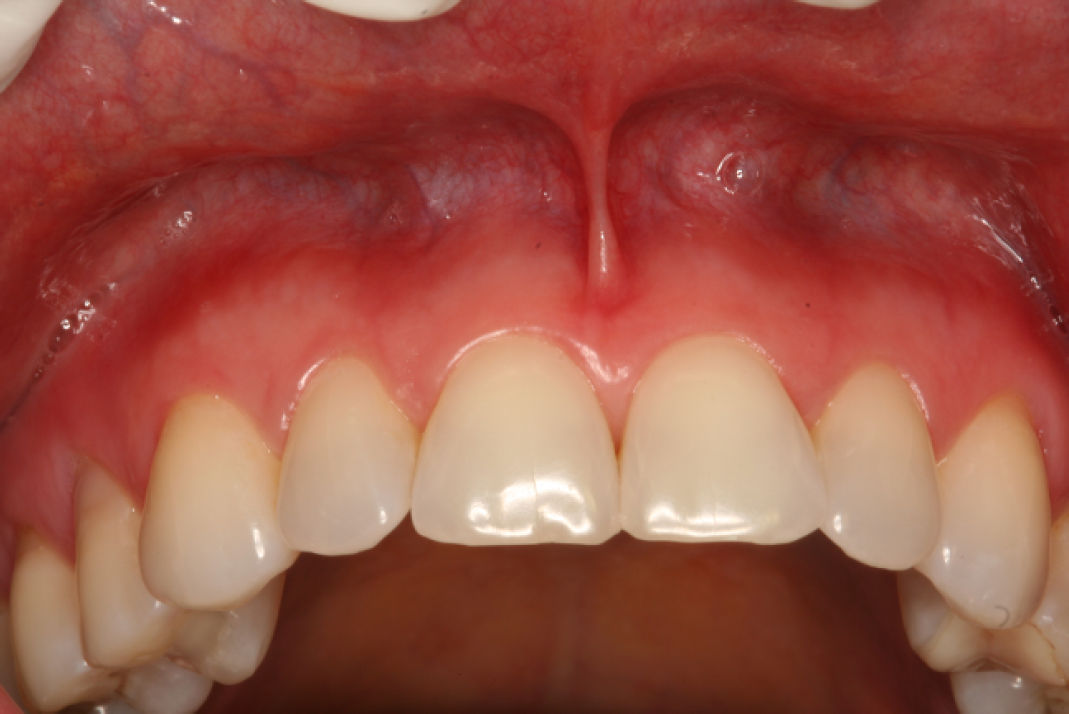

Фото 2. Через 3 дня после прекращения использования зубной пасты, отмечается полное исчезновение поражений

Эти реакции были связаны с изменением формулы продукта, что также отмечено в официальном заявлении агентства. Подозреваемая причинная связь была подтверждена полным исчезновением поражений в течение 3 дней после прекращения использования пасты, без рецидивов на момент наблюдения.